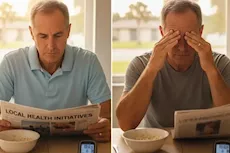

ماذا يحدث للكبد عند نقص الكولين بالجسم؟

تأثير نقص الكولين على الكبد

يجب الحفاظ على توازن الكولين بالجسم، لأن انخفاضه عن المعدل الطبيعي يشكل خطرًا كبيرًا على صحة الكبد.

عندما تقل مستويات الكولين بالجسم، يزداد خطر الإصابة بمرض الكبد الدهني، لأن دهون يزداد تراكمه في الكبد عند نقص هذا العنصر الغذائي بالجسم.